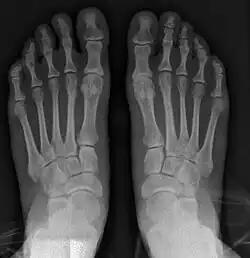

- For severe bunion deformity correction (Fig. 7)

- For recurrence correction after osteotomy procedure (Fig. 8)

Late deformity recurrence can happen after osteotomy (bone-breaking) procedures because osteotomy surgeries do not specifically stabilize first metatarsal bone.